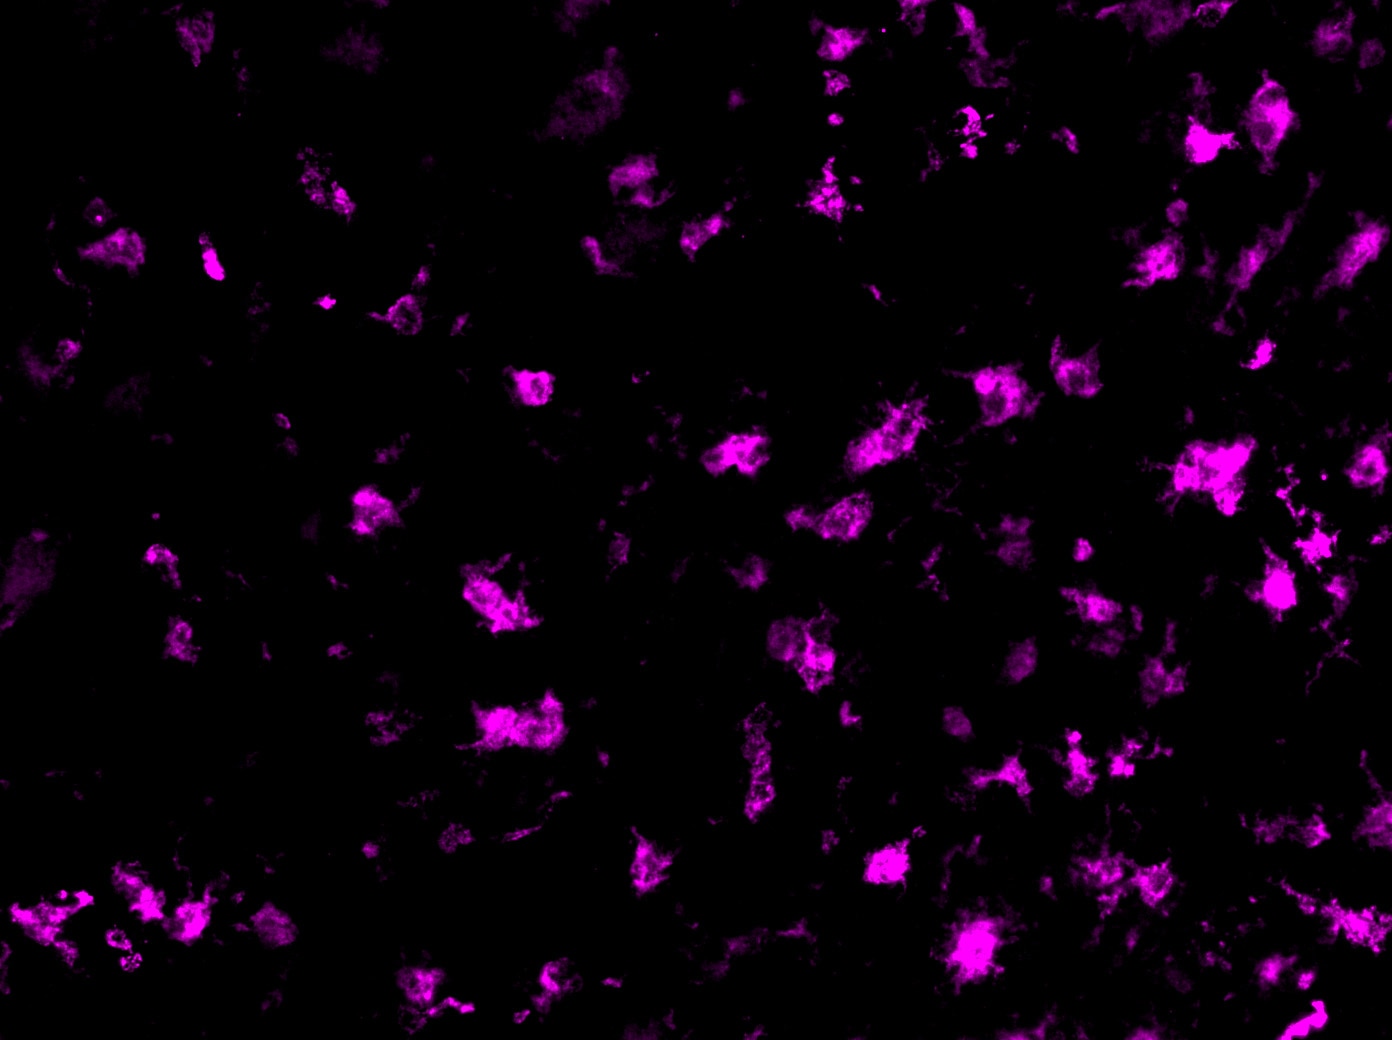

MMR/CD206 in Mouse Lung. MMR/CD206 was detected in perfusion fixed frozen sections of mouse lung using Goat Anti-Mouse MMR/CD206 Antigen Affinity-purified Polyclonal Antibody (Catalog # AF2535) at 25 µg/mL overnight at 4 °C. Tissue was stained using the NorthernLights™ 493-conjugated Anti-Goat IgG Secondary Antibody (green; Catalog # NL003) and counterstained with DAPI (blue). Specific staining was localized to cytoplasm of macrophages. View our protocol for Fluorescent IHC Staining of Frozen Tissue Sections.